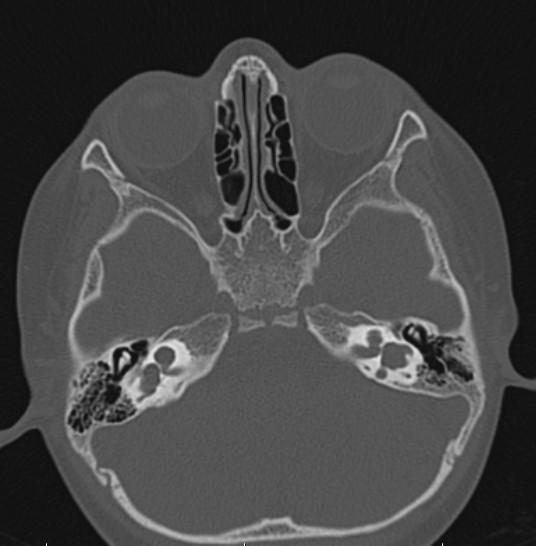

*2-year-old child with hearing loss.

Answer: Bilateral incomplete partition Type I (cystic cochleovestibular anomaly)

Axial MR and CT images show the cystic bilateral cochlea (red arrow) and the dilated cystic bilateral vestibule (yellow arrow). The vestibular aqueduct is normal in size.